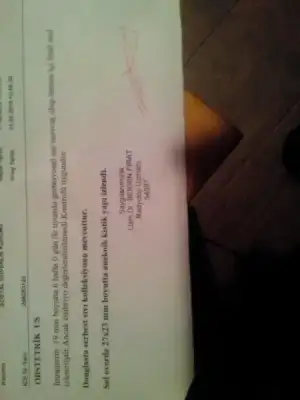

Ya bu doktorlar bu karanlık görüntüden kanamayı falan nasıl buluyorlar. Hayret doğrusu.Eki Görüntüle 1771039 Kızlar bu doktora ilk gittiğimizde kanamam varken ki kese. İğnelerden ve iki gün sonra daha bi toplu fasulye gibiydi. Onun kağıdını vermedi

güzelim bu sadcee fotograf ama çekip anında hareketli onların anlayabilecekleri bir akış oluyor demek ki.Ya bu doktorlar bu karanlık görüntüden kanamayı falan nasıl buluyorlar. Hayret doğrusu.